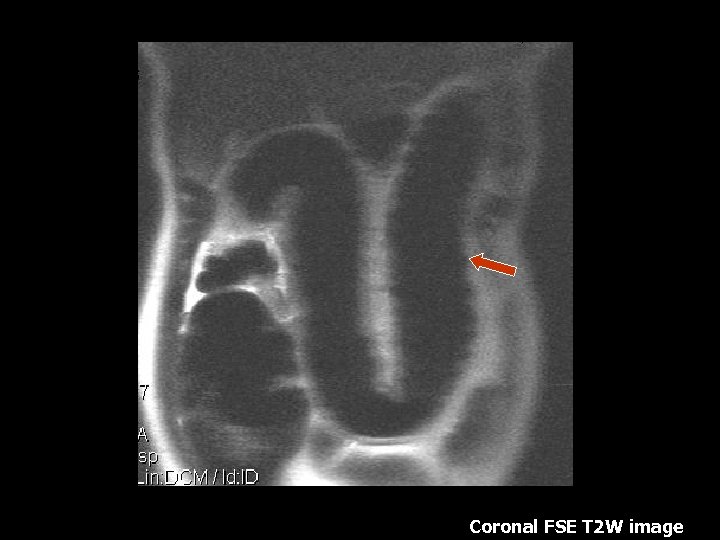

Multiple stones in the infundibulum of the gallbladder compressing the proximal common bile duct and causing intrahepatic biliary dilatation. Distal common bile duct is normal in caliber. Coronal SSFSE T 2 w axial image

Mirrizi Syndrome • Uncommon cause of obstructive jaundice that occurs in the setting of cholelithiasis and cholecystitis(10). • Obstruction of the CHD is caused by an impacted stone within the cystic duct(10). • Predisposing factors include low insertion of the cystic duct into the CHD. The cystic duct and the CHD travel in a sheath together before joining to become the CBD(10).